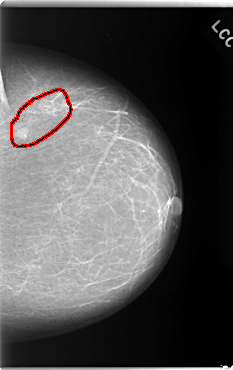

C_0132_1.LEFT_CC

LEFT_CC LINES 5920 PIXELS_PER_LINE 3728 BITS_PER_PIXEL 12 RESOLUTION 50 OVERLAY

FILE: C_0132_1.LEFT_CC.OVERLAY

TOTAL_ABNORMALITIES 1

ABNORMALITY 1

LESION_TYPE CALCIFICATION TYPE PLEOMORPHIC DISTRIBUTION CLUSTERED

LESION_TYPE MASS SHAPE OVAL MARGINS CIRCUMSCRIBED

ASSESSMENT 4

SUBTLETY 5

PATHOLOGY MALIGNANT

TOTAL_OUTLINES 1

BOUNDARY